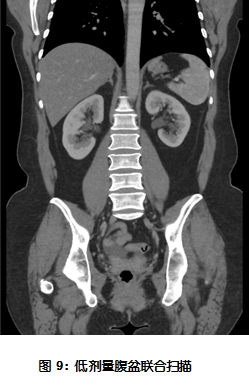

扫描条件: Axial scanning

KV Assist 100KV 22.4NI DLP 240mGyNaN 3.5mSv 这幅图像剂量低,图像空间分辨率高,密度分辨率好,没有伪影。